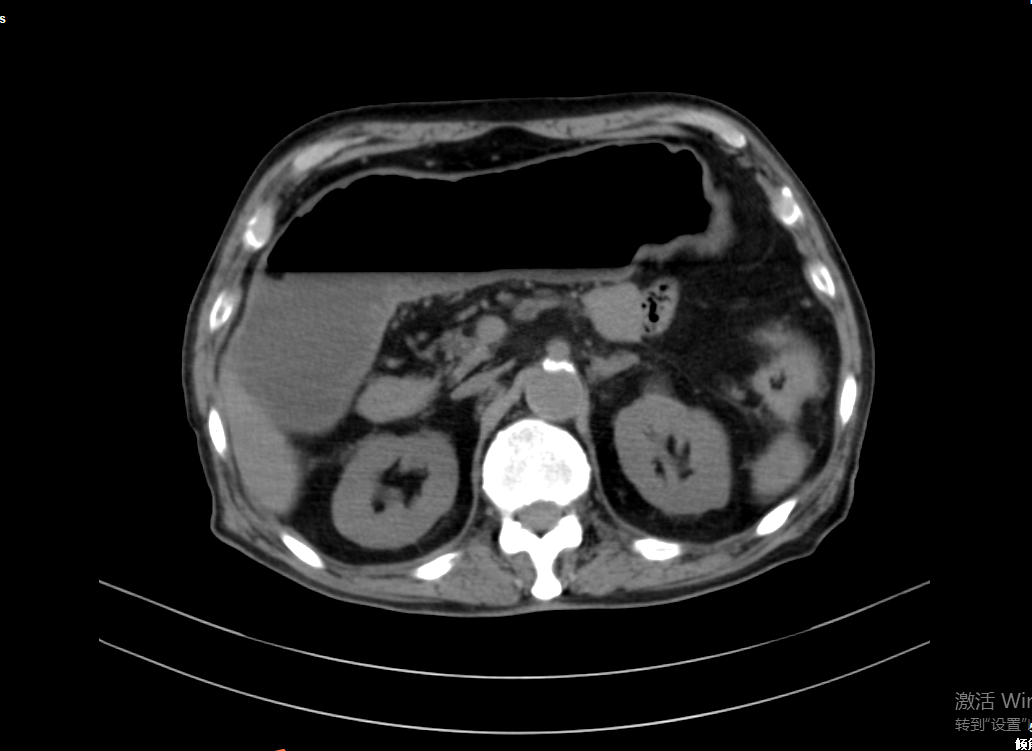

CT示肠道梗阻脾胃病科主任叶浩将病情告知患者家属,家属考虑患者年事已高,如果行外科手术,创伤较大,难以恢复,拒绝了手术治疗方案,转而希望行保守治疗。但患者营养情况差,如果肠梗阻无法解除,将有肠缺血、坏死、穿孔危险,危及生命。为此,叶浩与患者家属耐心解释,经患者家属同意后,决定为患者实施内镜下结肠支架置入术。